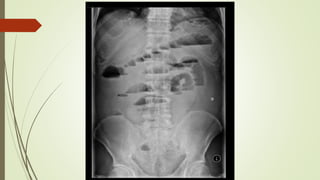

IN PLAIN XRAY

Dilated bowel loops

 small bowel > 3 cm

 Proximal large bowel > 9 cm

 Transverse colon > 5.5 cm

 Sigmoid colon > 5 cm

Multiple air fluid level

step ladder pattern

Jejunum : Valvulae conniventes - concertina or ladder effect

Ileum : featureless

Colon : Haustral folds

IMAGING IN PLAIN XRAY Dilatedbowel loops  small bowel > 3 cm  Proximal large bowel > 9 cm  Transverse colon > 5.5 cm  Sigmoid colon > 5 cm Multiple air fluid level step ladder pattern Jejunum : Valvulae conniventes - concertina or ladder effect Ileum : featureless Colon : Haustral folds